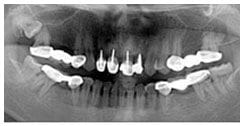

X 光片

術前X光片